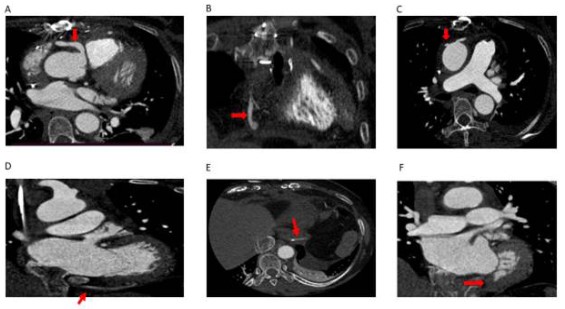

Coronary cameral fistula in a 57year old female patient who subsequently underwent surgical repair. Post-procedural axial (a, b, c, d, e & f)) CT coronary angiogram images show a right coronary artery arising from the right sinus of Valsalva (arrow in a) coursing towards the right side and abruptly ending in the mediastinum, coronal view (b) shows the right coronary artery stump closed with vein patch (arrow in b) in the mediastinum. Note one reversed saphenous vein graft arising from the ascending aorta on the right side (straight arrow in c) coursing inferiorly (arrow in d) and anastomosed to PDA (arrow in e). Note there is no visualization of the residual fistulous tract between the RCA and left ventricular chamber (arrow in f) owing to the successful repair of the coronary cameral fistula.

Figure 3: